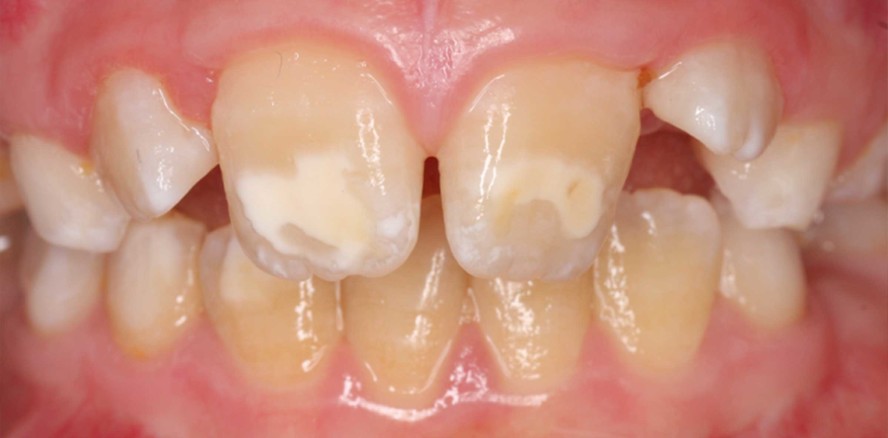

Foto: © Prof. Dr. Katrin Bekes

Die MIH tritt klassischerweise an einem bis zu vier ersten bleibenden Molaren mit oder ohne Einbezug der bleibenden Inzisiven auf. Charakteristisch für die Erkrankung sind umschriebene Opazitäten von weißer, gelblicher oder brauner Farbe im Zahnschmelz und ggf. fortschreitende posteruptive Schmelzeinbrüche sowie möglicherweise das Auftreten von Überempfindlichkeiten an den Zähnen.